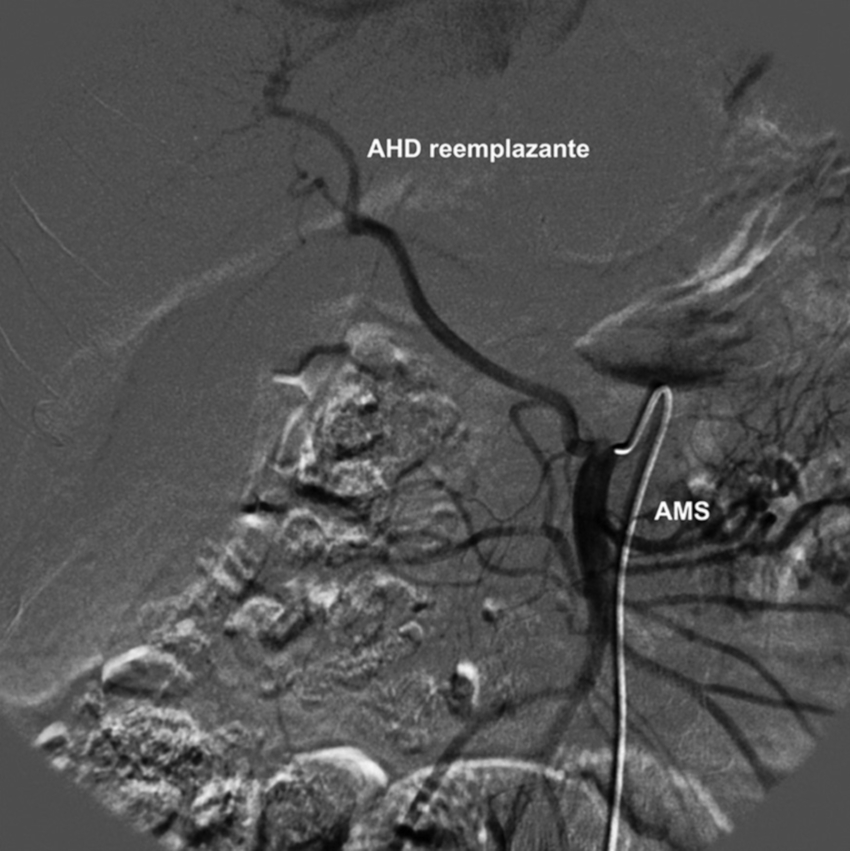

Se ha utilizado la clasificación de Michels5 y consideramos oportuno, en primer lugar, definir los términos “aberrante”, “accesoria” y “reemplazante”. El término “aberrante” se aplica a aquellas arterias hepáticas que aparecen en forma variable, originándose en un sitio distinto al del vaso normal (por ejemplo, la aorta, la AMS, la arteria mesentérica inferior, etc.), que clásicamente no se encuentran en la región estudiada. A las arterias hepáticas aberrantes se las dividió en dos tipos: “accesoria” y “reemplazante”.

Las arterias hepáticas aberrantes “accesorias” son aquellas que, originándose en un sitio distinto del normal, se presentan cercanas al vaso de anatomía clásica, sumándose a este para la vascularización de un sector determinado del hígado. En cambio, las arterias hepáticas aberrantes “reemplazantes” son aquellas que se encuentran presentes en ausencia del vaso de disposición normal, originándose en un sitio distinto del habitual. De esta manera, estas arterias reemplazan la función de las arterias de origen normal y se encargan por sí solas de la vascularización de un determinado sector hepático (Fig. 3). Asimismo, la presencia de una rama venosa portal sin una arteria correspondiente indica una anatomía vascular reemplazada o accesoria, o vasos colaterales hepatófugos transhepáticos11.

Tipo 3: AHD aberrante con origen en la AMS. AHI con origen en la AHC (Figs. 6 y 7).

La población estudiada fue de 275 pacientes, con una edad mediana de 58.5 años y de sexo masculino el 73.1% (n = 201). Se han constatado las variantes tipo 1 (normal) de anatomía de la arteria hepática en 192 casos (69.8%), tipo 2 en 18 casos (6.5%), tipo 3 en 19 casos (6.9%), tipo 4 en 7 casos (2.5%), tipo 5 en 4 casos (1.5%), tipo 6 en 3 casos (1.1%), tipo 7 en 2 casos (0.7%), tipo 8 en 7 casos (2.5%), tipo 9 en 17 casos (6.2%).